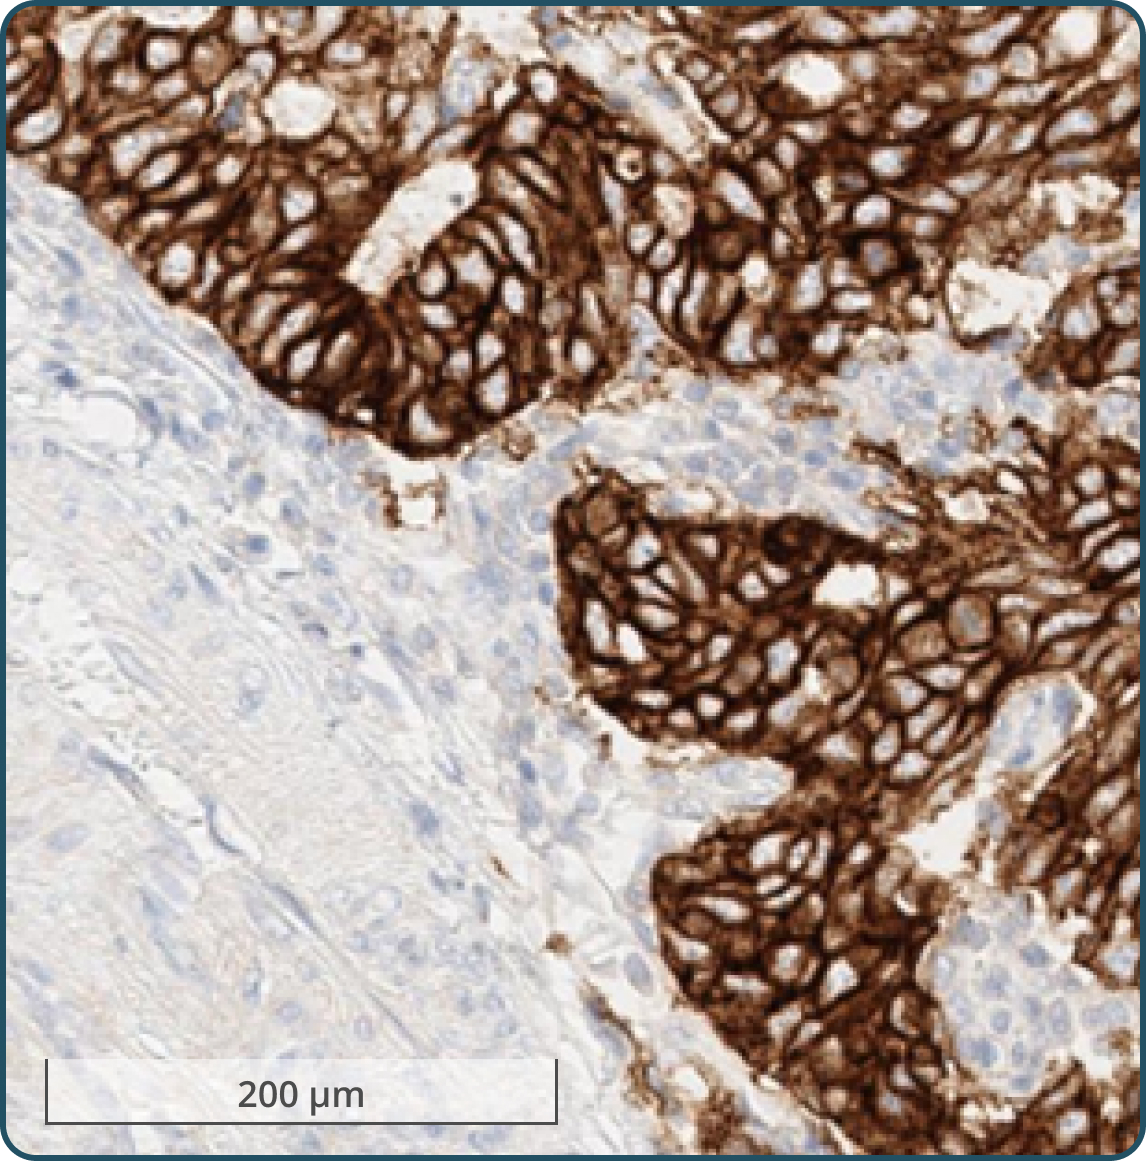

Tumor cells exhibiting moderate (2+) to strong (3+) membranous staining3-5

Any tumor cells with moderate (2+) to strong (3+) membranous staining, including any of the following:

No tumor cells with moderate (2+) to strong (3+) membranous staining OR tumor cells only exhibiting: